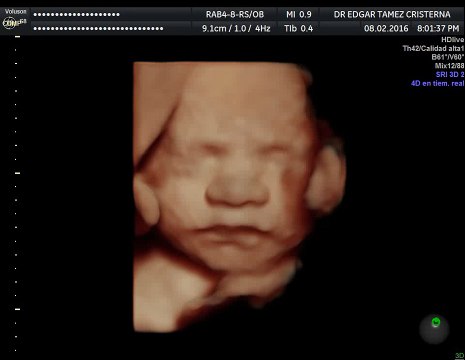

¿Por qué la paciente se debe realizar un ultrasonido entre las semanas 30-32 de embarazo?